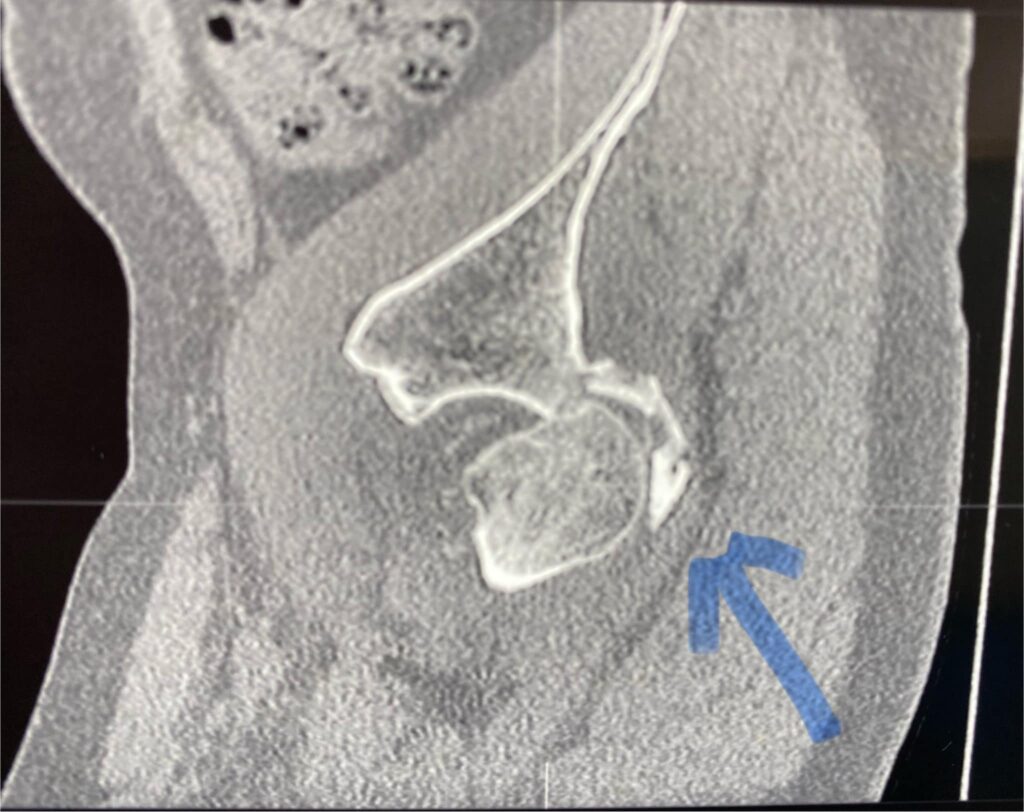

Тут вы видите рентгенограммы двух пациентов. В одном случае ранение голени у коленного сустава. В другом случае у сустава голеностопного с переломом костей. Поэтому там пластина еще стоит.

Обоим раненым (а каждый из них лечится по полгода уже) проведены по несколько операций дебридмента («чистка» кости и мягких тканей). К сожалению, это не остановило инфекцию.

В общем, все чаще и чаще приходится травматологам в Украине применять Bonalive. Это заменитель кости с антибактериальным действием. Только вот действует этот заменитель (финского производства) не за счет антибиотиков. Их в нем нет. А за счет того, что резко меняет Ph среды в кислую сторону. Бактерии погибают, привыкания к этому заменителю нет и быть не может (пока и если не появится какой-то новый, доселе неизвестный микроб), рост же собственной кости резко стимулируется.

Bonalive, как и всякий современный препарат высокотехнологичного производства, очень и очень дорог. Вот такой шприц-контейнер, как на фото, с 10 «кубиками» препарата стоит 500 евро (плюс-минус несколько процентов в зависимости от величины поставки).

Эти двое пациентов, чьи рентгенограммы вы видите, были прооперированы Председателем нашей Ассоциации AO Trauma Ukraine Олександром Рихтером в одном из военных госпиталей на западе Украины. Все зажило отлично.

Для первого раненого хватило 10 кубических сантиметров Bonalive, на второго – там, где пластина, ушло 20 «кубиков». Итого, в дополнение ко всему прочему – это 1500 евро.